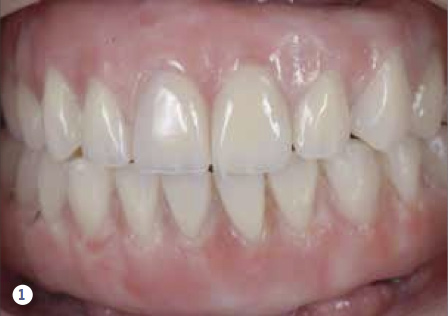

Fig 1. Clinical view of an implant-supported, screw-retained, full-mouth reconstruction.

Figure 1